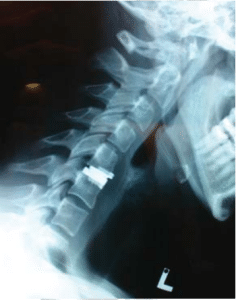

Lateral cervical spine flexional and extension x-rays show good movement of the cervical spine, this is important if we are planning to insert an artificial disc.